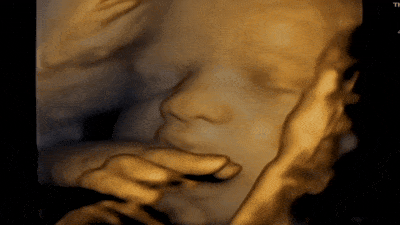

Our state-of-the-art ultrasound technology gives you a front-row seat to your baby’s world. From tiny yawns and gentle stretches to blinking, swallowing, and little finger wiggles, our 3D, 4D, and HD ultrasounds capture these once-in-a-lifetime moments with stunning clarity and detail.

Brings images to life with real-time motion, letting you watch your baby smile, yawn, or move inside the womb.